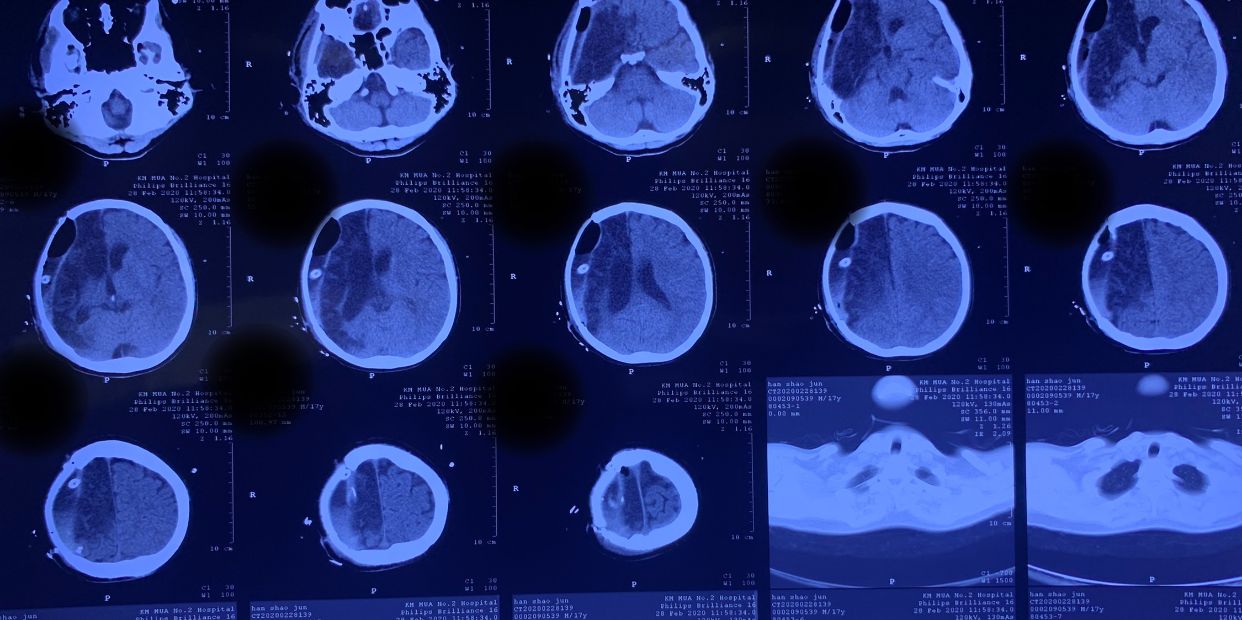

因病情危重,家属决定转院。于伤后11小时送至德宏州医院进一步治疗。患者于10月16日23时左右突发右侧瞳孔散大,急诊复查头颅CT示右侧额颞顶枕大面积脑梗死。

再次手术后于10月18日复查CT

10月24日再次复查头颅CT:中线回移,脑室系统逐渐显示。此时骨窗压力亦明显下降。